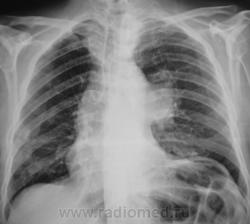

Пол пациента: Мужской пол Тип патологии: Другое Область исследования: Грудная клетка и верхние дыхательные пути Методы исследования: Rg Взят на контроль после флюорографии. https://radiomed.ru/sites/default/files/styles/case_slider_image/public/user/12/2.pb160005.jpg?itok=FLcZ_Iph ID:9374 Ср, 17/11/2010 - 07:54 #1 Игорь Иванович Не на сайте Был на сайте: 3 года 9 месяцев назад Зарегистрирован: 23.01.2010 - 14:56 Публикации: 3695 Какакя-то аневризма. Ср, 17/11/2010 - 10:40 #2 Сан Саныч1 Не на сайте Был на сайте: 11 месяцев 1 неделя назад Зарегистрирован: 07.06.2010 - 21:17 Публикации: 2114 Надо томографировать. Хочешь сделать что-то нормально - сделай это сам! Ср, 17/11/2010 - 16:46 #3 Виктор ВК Не на сайте Был на сайте: 14 лет 8 месяцев назад Зарегистрирован: 01.10.2010 - 15:34 Публикации: 114 и подворот и переломы)) а может и центральные дела Виктор Владимирович К. Ср, 17/11/2010 - 20:29 #4 Катенёв Валенти... Не на сайте Был на сайте: 7 лет 1 неделя назад Зарегистрирован: 22.03.2008 - 22:15 Публикации: 54876 Обработка боковой рентгенограммы. Приложения: Ср, 17/11/2010 - 20:30 #5 Катенёв Валенти... Не на сайте Был на сайте: 7 лет 1 неделя назад Зарегистрирован: 22.03.2008 - 22:15 Публикации: 54876 Сан Саныч1 wrote: Надо томографировать. Приложения: Ср, 17/11/2010 - 22:34 #6 Віктор Не на сайте Был на сайте: 12 лет 8 месяцев назад Зарегистрирован: 13.10.2010 - 22:18 Публикации: 33 Думаю , киста вилочковой железы ( был похожий случай ). Чт, 18/11/2010 - 00:44 #7 Дарья Не на сайте Был на сайте: 15 лет 1 неделя назад Зарегистрирован: 22.09.2010 - 22:33 Публикации: 98 центральный рак тут, какие кисты Чт, 18/11/2010 - 01:08 #8 Катенёв Валенти... Не на сайте Был на сайте: 7 лет 1 неделя назад Зарегистрирован: 22.03.2008 - 22:15 Публикации: 54876 Вы думаете, что тут центральный рак? Чт, 18/11/2010 - 03:43 #9 Виктор ВК Не на сайте Был на сайте: 14 лет 8 месяцев назад Зарегистрирован: 01.10.2010 - 15:34 Публикации: 114 средостение объективно смещено вправо..видимо это образование его оттесняет..во всяком случае центральный процесс исключть пока нельзя... Виктор Владимирович К. Чт, 18/11/2010 - 09:23 #10 Дарья Не на сайте Был на сайте: 15 лет 1 неделя назад Зарегистрирован: 22.09.2010 - 22:33 Публикации: 98 чего так купол выско стоит? и на томограммах сдавлен верхнедолевой Чт, 18/11/2010 - 17:02 #11 Катенёв Валенти... Не на сайте Был на сайте: 7 лет 1 неделя назад Зарегистрирован: 22.03.2008 - 22:15 Публикации: 54876 Дарья wrote: чего так купол выско стоит? и на томограммах сдавлен верхнедолевой Значит, должон быть ателектаз, или на "худой конец" гиповентиляция? Чт, 18/11/2010 - 21:29 #12 Катенёв Валенти... Не на сайте Был на сайте: 7 лет 1 неделя назад Зарегистрирован: 22.03.2008 - 22:15 Публикации: 54876 Итак, три мнения: - какая то аневризма; - киста; - центральный рак. Сб, 04/12/2010 - 19:30 #13 Makcimalist Не на сайте Был на сайте: 11 лет 8 месяцев назад Зарегистрирован: 08.05.2010 - 14:28 Публикации: 1994 Катенёв Валентин Львович wrote: Итак, три мнения: - какая то аневризма; - киста; - центральный рак. И чем дело кончилось?.. (+1 за центр. образование левого лёгкого) -------------- "Просто, по видимости, не видеть логики в очевидных вещах - это тоже одно из свойств некоторых умов, наряду с грустными думами о свойствах ума других." © Vega 08/10/2011 Вс, 05/12/2010 - 11:50 #14 Катенёв Валенти... Не на сайте Был на сайте: 7 лет 1 неделя назад Зарегистрирован: 22.03.2008 - 22:15 Публикации: 54876 Дело кончилось аневризмой. Ср, 08/12/2010 - 21:09 #15 Makcimalist Не на сайте Был на сайте: 11 лет 8 месяцев назад Зарегистрирован: 08.05.2010 - 14:28 Публикации: 1994 Катенёв Валентин Львович wrote: Дело кончилось аневризмой. Спасибо, за законченный случай! -------------- "Просто, по видимости, не видеть логики в очевидных вещах - это тоже одно из свойств некоторых умов, наряду с грустными думами о свойствах ума других." © Vega 08/10/2011 Пт, 10/12/2010 - 22:27 #16 Игорь Иванович Не на сайте Был на сайте: 3 года 9 месяцев назад Зарегистрирован: 23.01.2010 - 14:56 Публикации: 3695 Катенёв Валентин Львович wrote: Дело кончилось аневризмой. На вскрытии? Пт, 10/12/2010 - 22:34 #17 Катенёв Валенти... Не на сайте Был на сайте: 7 лет 1 неделя назад Зарегистрирован: 22.03.2008 - 22:15 Публикации: 54876 Да. Сб, 11/12/2010 - 12:04 #18 Игорь Иванович Не на сайте Был на сайте: 3 года 9 месяцев назад Зарегистрирован: 23.01.2010 - 14:56 Публикации: 3695 Тогда выставлю до пары.На момент прохождения флгр. был еще жив...Приложения: Сб, 11/12/2010 - 15:49 #19 Катенёв Валенти... Не на сайте Был на сайте: 7 лет 1 неделя назад Зарегистрирован: 22.03.2008 - 22:15 Публикации: 54876 Да, аналогия прослеживается, особеннос томограммами.

Какакя-то аневризма.

средостение объективно смещено вправо..видимо это образование его оттесняет..во всяком случае центральный процесс исключть пока нельзя...

чего так купол выско стоит?

и на томограммах сдавлен верхнедолевой

Значит, должон быть ателектаз, или на "худой конец" гиповентиляция?

Итак, три мнения:

- какая то аневризма;

- киста;

- центральный рак.

Дело кончилось аневризмой.

На вскрытии?

Да.